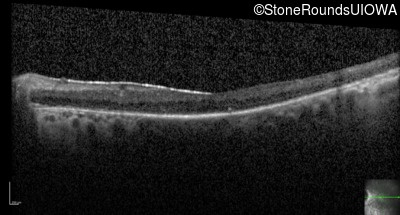

Optical Coherence Tomography - Left - 20/40 -1

Exemplar / OCT Stack

OCT Stack